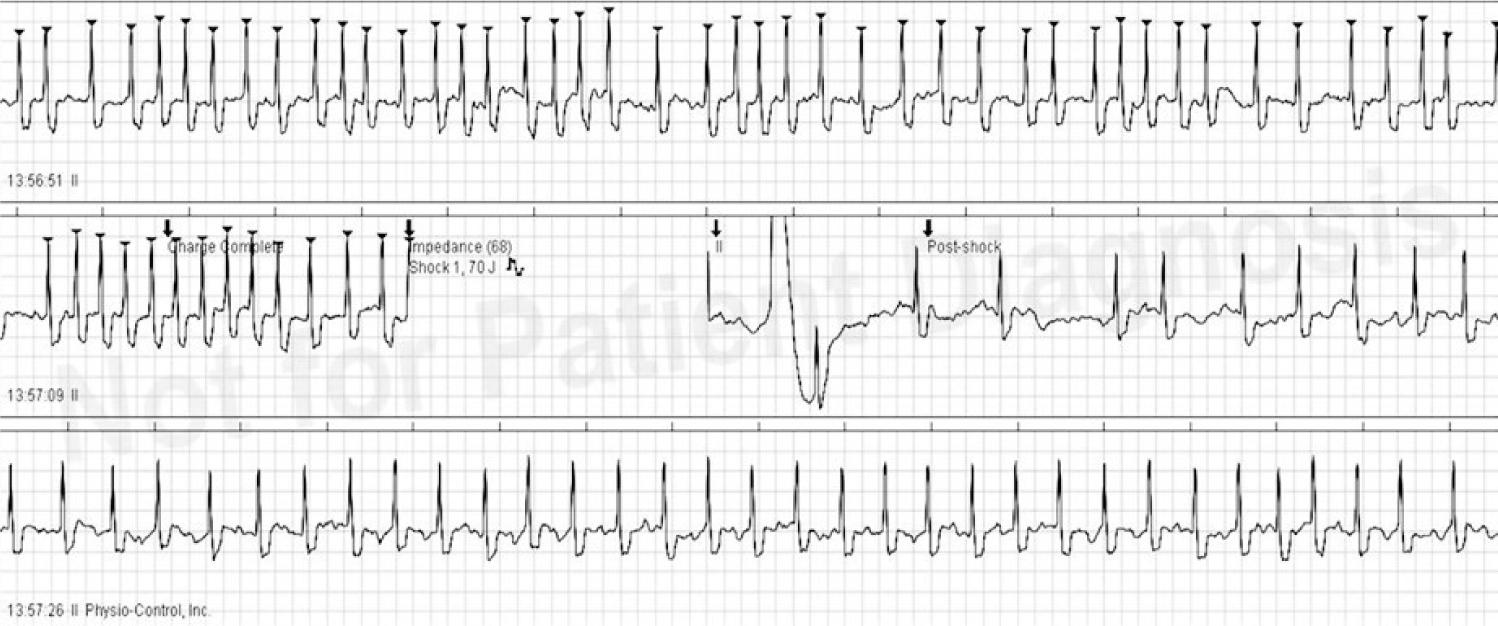

Fig. 1